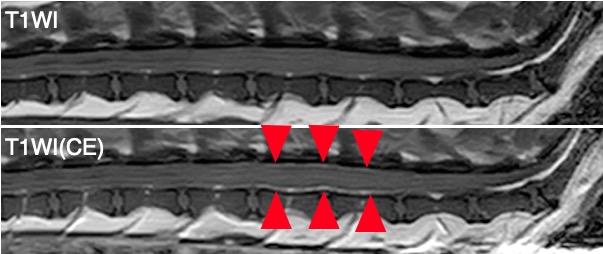

MRIではL4-5椎体レベルの脊髄髄膜において造影剤にて増強される病変が認められました。

腰部のMRI。上画像:造影剤投与前のT1強調画像、下画像:造影剤投与後のT1強調画像。 造影剤で増強された髄膜が認められる(赤矢頭)。